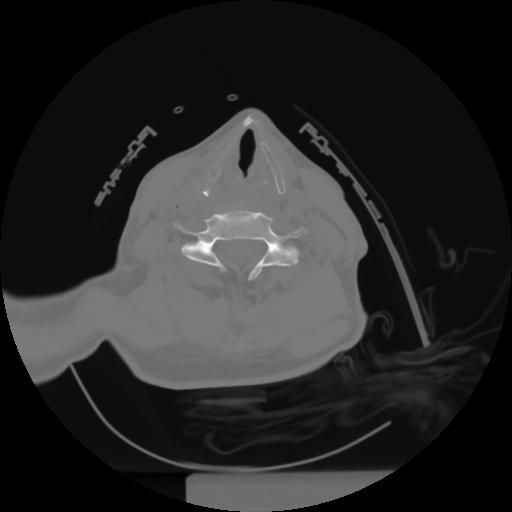

10 P.BLANDAS,,Axial,2.0,P.BLANDAS,,